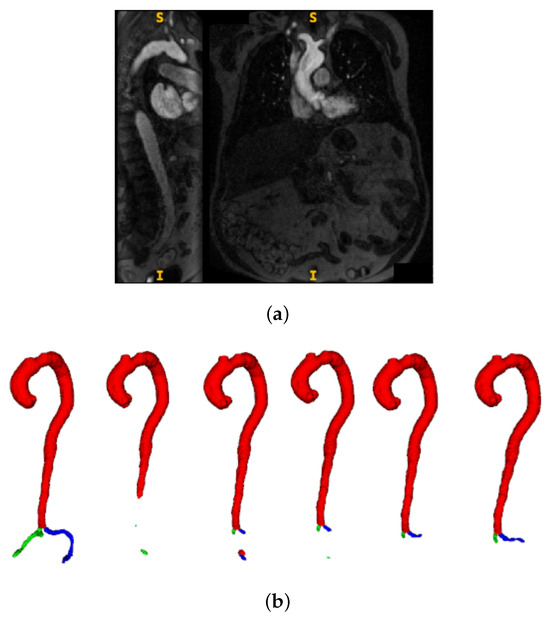

- Using a dataset of paired pre- and post-contrast scans, a modality ablation study is performed to systematically evaluate the distinct and combined contributions of each imaging modality. To the best of authors’ knowledge, this is the first such evaluation in the context of CMR-based TAVI planning.

3.3. Multimodal Ablation Study

4.3. Multimodal Ablation

- Impact of modality and pseudo-labels: The multimodal ablation study (Table 2) revealed post-contrast CMR as the most reliable input, delivering the highest Dice and lowest MAPE. By contrast, the inclusion of inferred cases slightly degraded performance, underscoring the sensitivity of segmentation models to label noise when pseudo-label confidence is not tightly controlled. The success of uncertainty-guided pseudo-labelling during active learning contrasted with blind inference performance, emphasizing that pseudo-labelling strategies require carefully designed confidence thresholds and quality control mechanisms.

- Model architecture vs. data quality: Differences between 3D U-Net and UMamba were modest compared to the impact of input modality. This suggests that improving data quality and curation may be more beneficial than pursuing marginal network refinements for this application. Surprisingly, combined pre- and post-contrast data did not consistently improve performance, suggesting current architectures may struggle with effective multimodal feature fusion or that alignment issues introduce artifacts.

- Limitations: The study was based on single-center data, which may limit generalizability across populations, scanner vendors, or imaging protocols. Performance on pre-contrast CMR remained substantially weaker, even when combined with post-contrast data, indicating that multimodal integration strategies require further refinement. Finally, as the pipeline is sequential, segmentation inaccuracies propagate to downstream diameter estimation, representing an area for future methodological improvement.